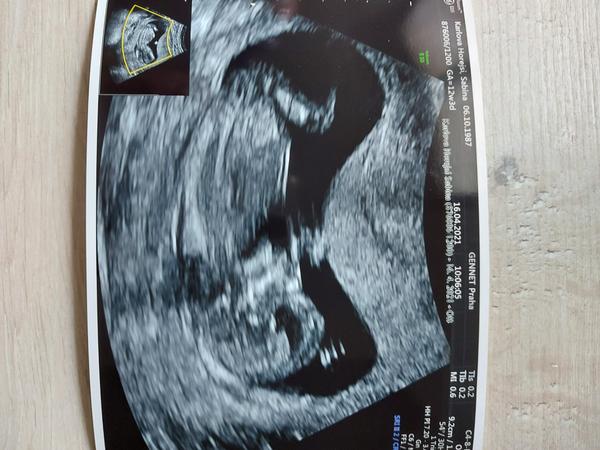

@sebinka123 tady z toho by to šlo poznat? 😁

@hawah 1 to má nějaké mazle a 2,3 typuju kluky

@sebinka123 👍 první dva kluci a třetí nejspíš bude taky, se brzo uvidí 😁